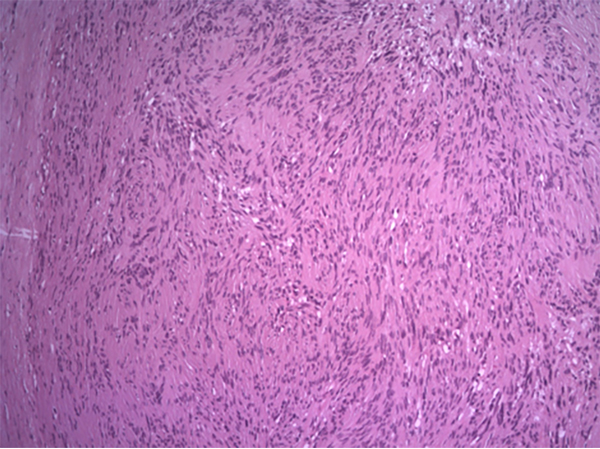

Luego, se localiza masa palpable correspondiente a tumoración, se efectúa incisión horizontal de piel y TCS; siguiendo las líneas de Langerhans, se evidencia nódulo bien delimitado, capsulado de consistencia firme, el cual se extrae en su totalidad con disección prolija y minuciosa, con su vaina en forma marginal (fig. 3). Se envía la pieza para su estudio anatomopatológico, con diagnóstico diferido de schwannoma (fig. 4).

Figura 4: Visión microscópica. 10X: cuerpos de Verocay (empalizada nuclear).